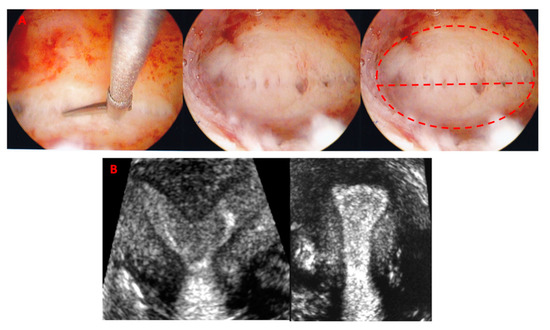

Indications for subseptation incision included prior pregnancy loss and dysmenorrhea. Since no clear-cut cut-off was recommended for surgical intervention, we used the previously published 5.9 mm [11] and we applied the ASRM guidelines which conclude that: a) in a patient with infertility, prior pregnancy loss, or poor obstetrical outcome it is reasonable to consider septum incision with septum length <15 mm; and b) in a patient without infertility or prior pregnancy loss, it may be reasonable to consider septum incision following counseling regarding potential risks and benefits of the procedure [8]. In the subseptate uterus group, surgical incision was performed, regardless of the menstrual cycle phase, following standard operative technique with either cold scissors without diathermy or with a bipolar cutting needle with 30–50 W cutting current. Subseptations were resected from the lower tip towards the fundus, up to the line connecting the tubal ostia, along the line of separation between the anterior and posterior walls. Incision of the subseptation with separation of the anterior and posterior uterine walls was performed without excision of myometrial tissue and no myometrial specimen was obtained in any of the procedures. Figure 3A shows incision of a uterine subseptation using cold scissors and the resulting gain of the uterine cavity. All patients had an intrauterine balloon placed at the end of the surgical incision, which was kept in the cavity for a maximum of 4 days and removed in the office. Post-operatively, all patients received broad spectrum antibiotics and estrogen supplementation for 7 days (200 mcg/day estradiol transdermally, or 2 mg/day estradiol, orally). Four weeks after removal of the intrauterine balloon, a second 3-D ultrasound was obtained, to measure the cavity width and length, in addition to all the standard uterine measurements. This interval was found to be sufficient for the uterus to regain its shape after a subseptation incision, based on our previous studies [3,11].

3. Results

Figure 3. (A): surgical incision of a uterine subseptation with cold scissors (left) and resulting uterine cavity (center and right). The tubal ostia are not visualized before and soon after subseptation incision because of the wide cavity. (B): a 3-D ultrasound coronal view rendering of a subseptate uterus before and after surgical incision.